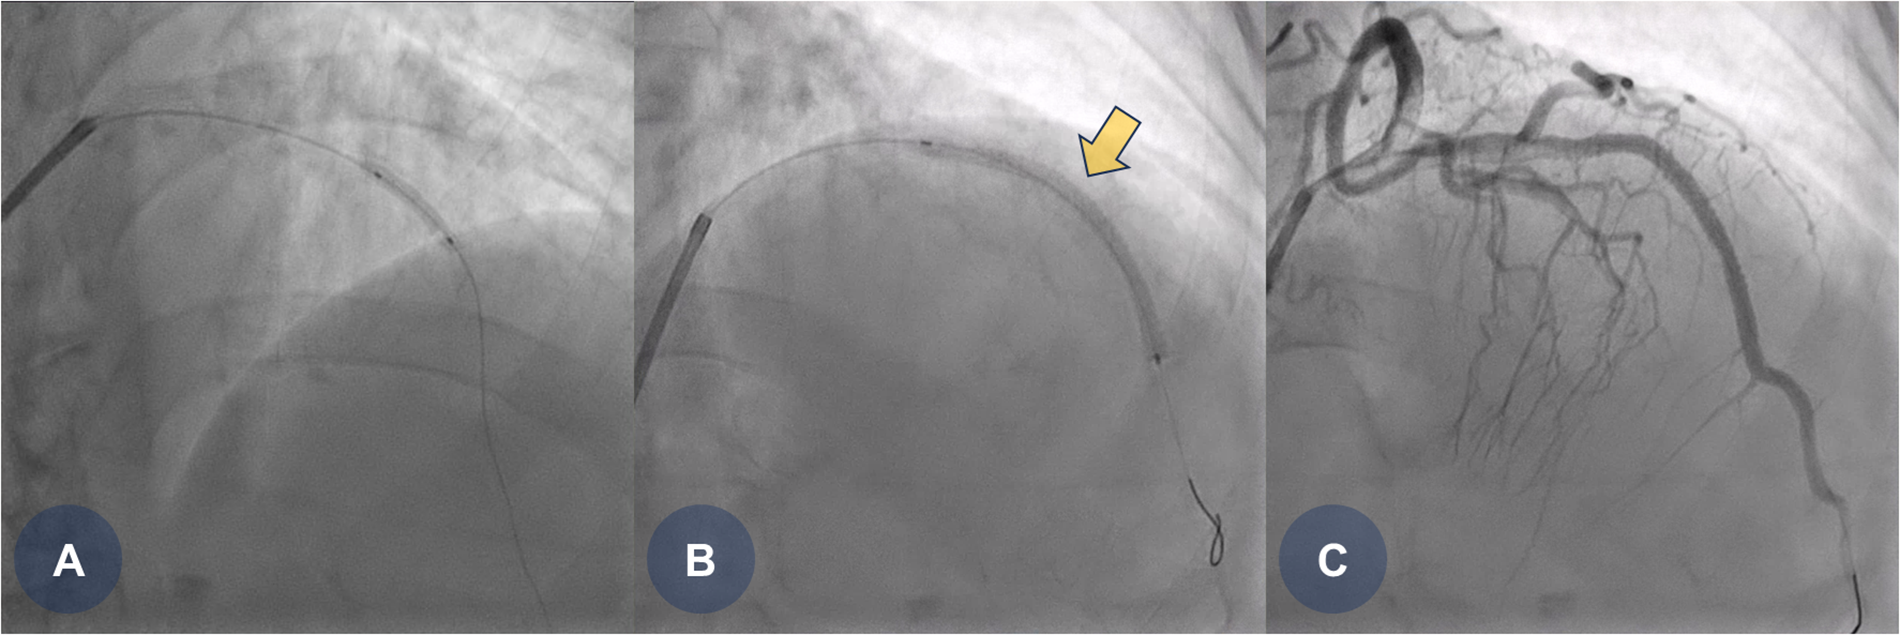

The patient was clinically suspected of having an ST-segment elevation myocardial infarction, prompting the immediate activation of the catheterization laboratory for primary PCI. Coronary angiography revealed a total occlusion in the mid-portion of the left anterior descending coronary artery. Pre-dilation ballooning was performed using a balloon catheter (Figure 1A), followed by the deployment of a durable-polymer everolimus-eluting stent (DP-EES; 3.0 × 48 mm, XIENCE™ Skypoint™; Abbott) at the site of the obstruction (Figures 1B,C, yellow arrow). Following successful PCI, the patient was admitted to the general ward for post-PCI management. She was treated with optimal medical therapy, including dual antiplatelet therapy (DAPT), beta-blockers, angiotensin receptor blockers, and high-intensity statins.

Figure 1

CAG findings during primary PCI. (A) Coronary angiography reveals total occlusion in the middle portion of the left anterior descending (LAD) artery, followed by pre-dilation ballooning using a 2.5 × 15 mm balloon catheter. (B) A durable-polymer everolimus-eluting stent (3.0 × 48 mm, XIENCE Skypoint; Abbott) is deployed at the middle portion of the LAD. (C) Final coronary angiography shows good stent expansion with no residual angiographic stenosis. CAG, coronary angiogram; LAD, left anterior descending coronary artery; PCI, percutaneous coronary intervention.